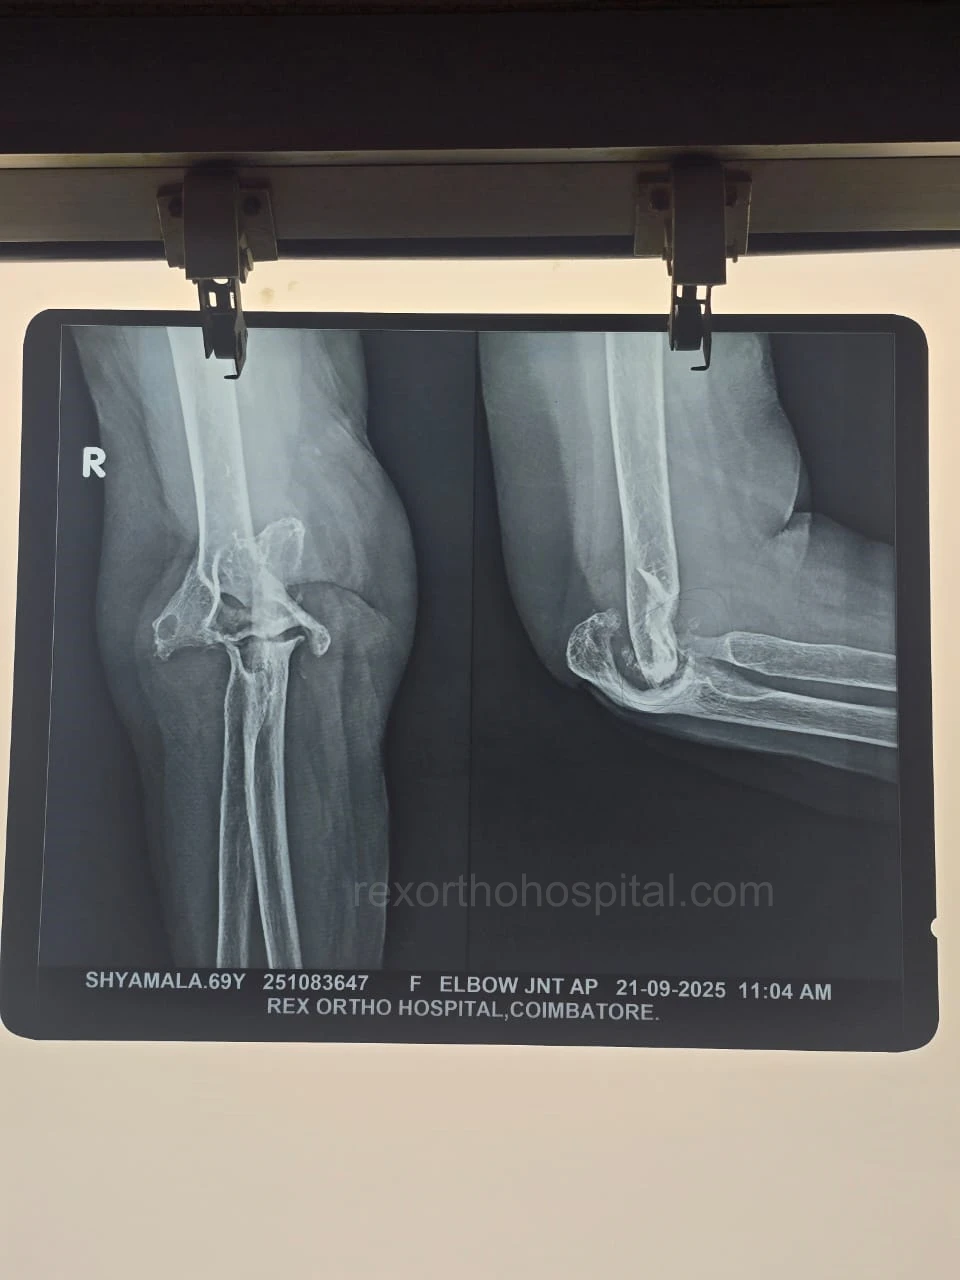

Elbow stiffness treatment aims to restore smooth movement and reduce pain caused by injury, arthritis, or long-term immobility. Our approach improves flexibility and helps regain everyday function.

From diagnosis to surgery and recovery, our team ensures you receive expert treatment and individual attention throughout your treatment journey